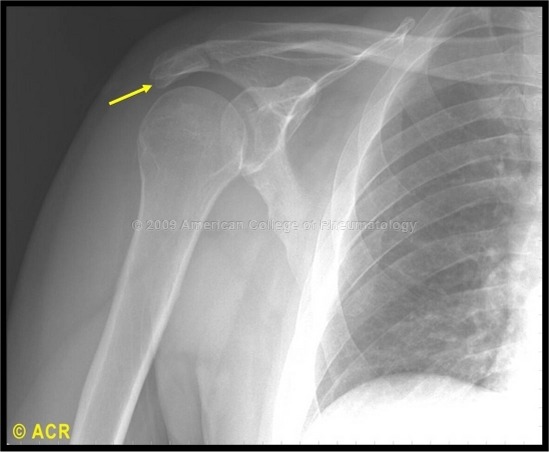

5. 견봉 부골(Os acromiale)이란 무엇인가?

견봉 부골(Os acromiale)은 견봉의 부골화 중심을 말한다. 견봉 부골은 25세 까지 성인 시기에 정상적으로 융합됨에도 불구하고, 몇몇은 융합되지 않은 상태로 남게 된다. 견봉 골절로 오해할 수 있기 때문에 하나의 실체로서 인식하는 것이 중요하다. 그리고 어깨충돌증후군과 회전근개파열의 높은 유병율과 이 견봉 부골과의 연관성이 있다.

견봉 부골(Os acromiale) (이미지 출처: http://images.rheumatology.org)